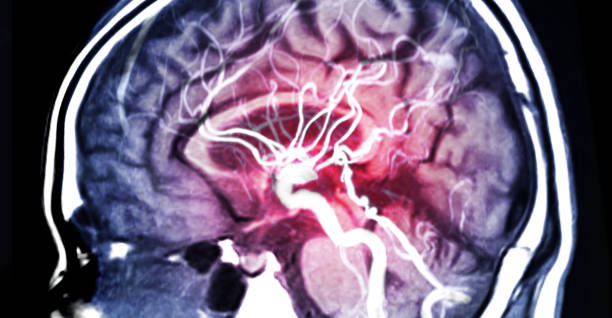

뇌졸중 증상

모야모야병의 가장 일반적인 증상 중 하나입니다. 뇌졸중 증상은 언어 장애, 인지 장애(기억력 감퇴, 학습 장애 등), 시각 장애(시야 손실, 양안 시력 장애), 운동 장애(양쪽 다리나 팔의 약화, 불균형, 혹은 어색한 움직임 등) 등이 있습니다.

반복성 뇌졸중

모야모야병은 뇌졸중 발생 위험이 높습니다. 반복적인 뇌졸중은 뇌조직 손상, 체력 저하, 기능 손상 등을 초래할 수 있습니다.